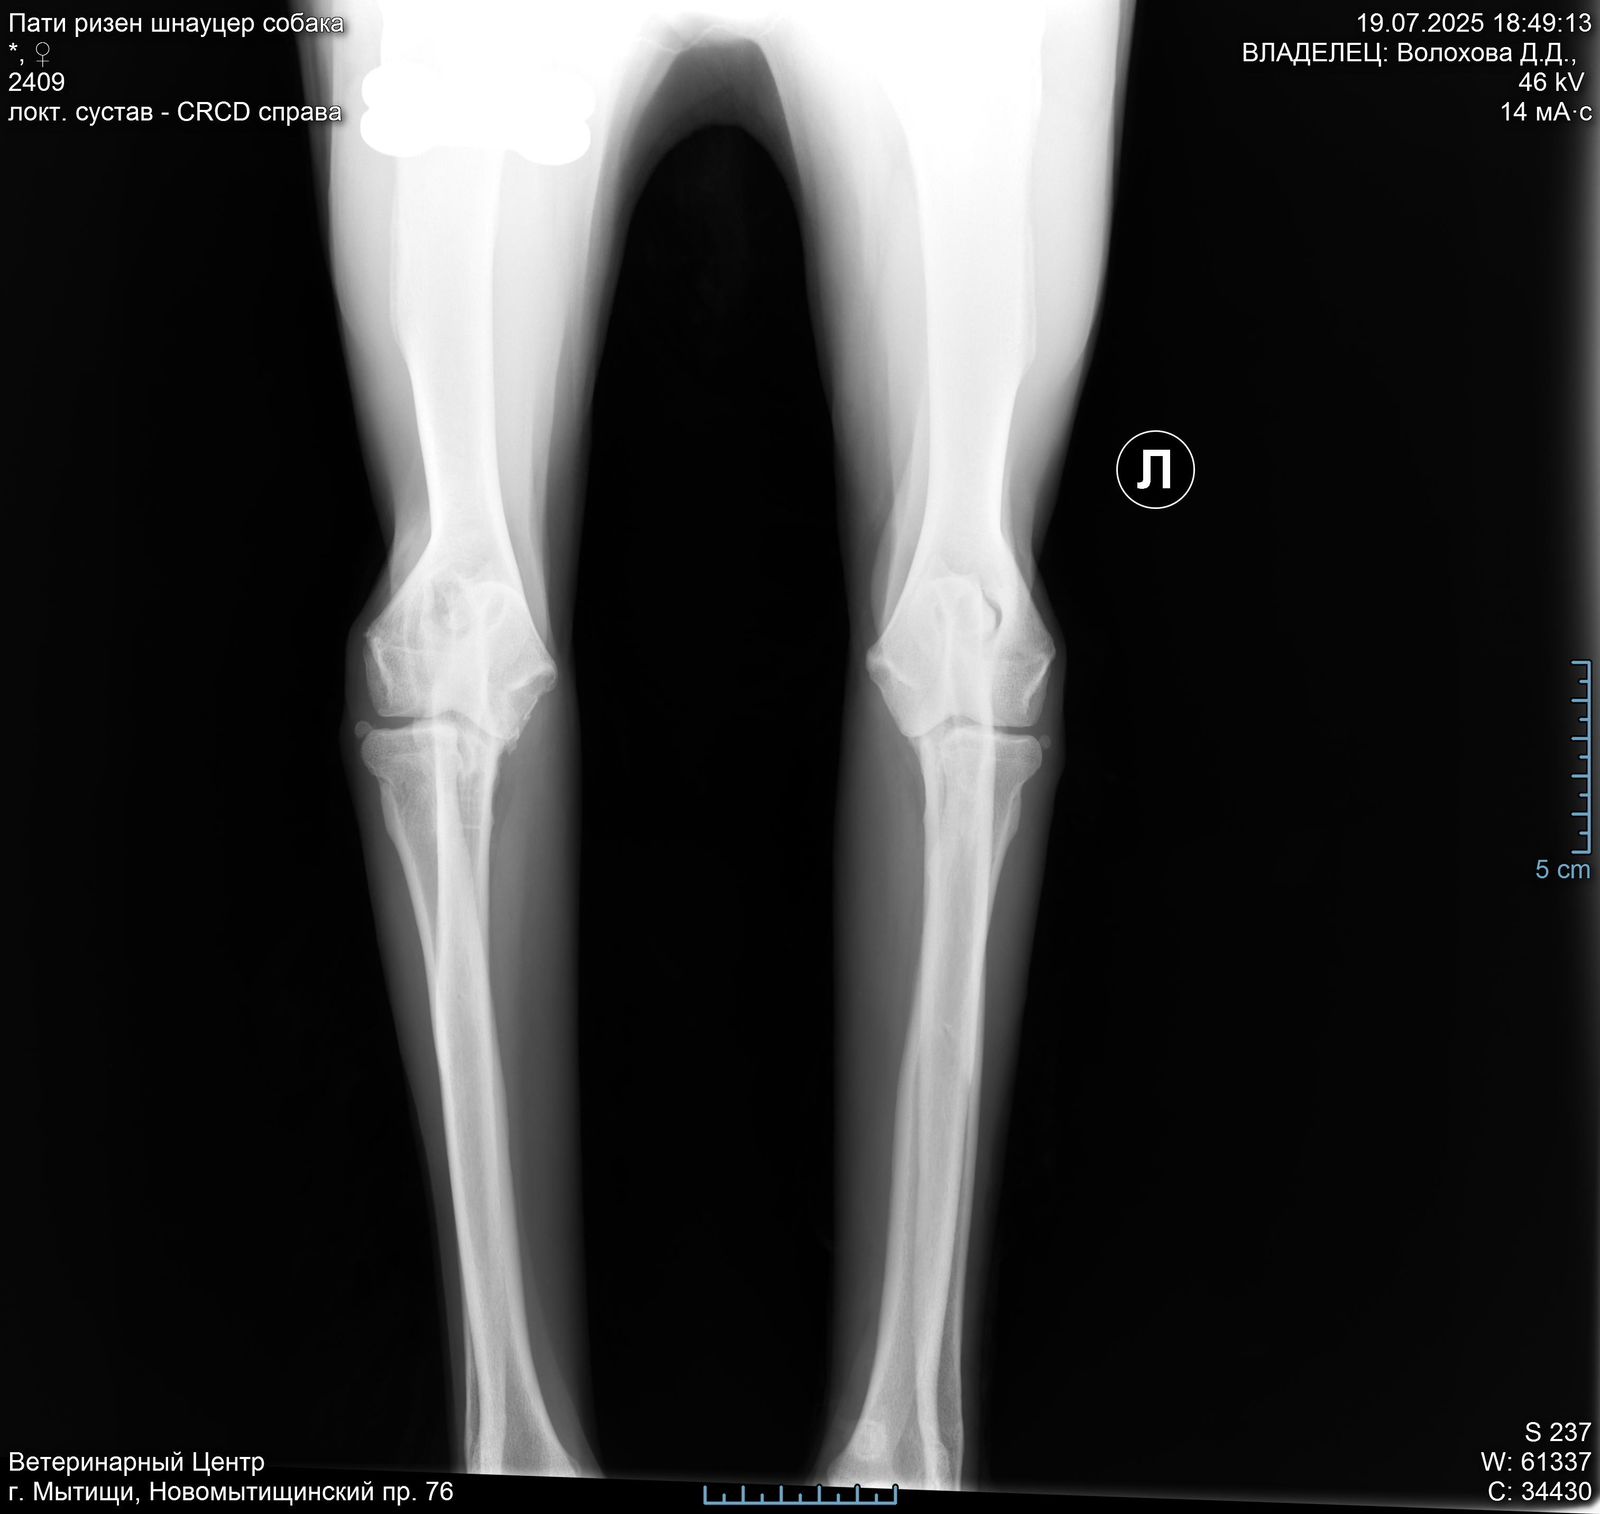

Лапа

В правом локтевом суставе у Пати болтается 2 осколка кости( от мыщелков).

Задние ноги не идеал, но портить жизнь не должны.